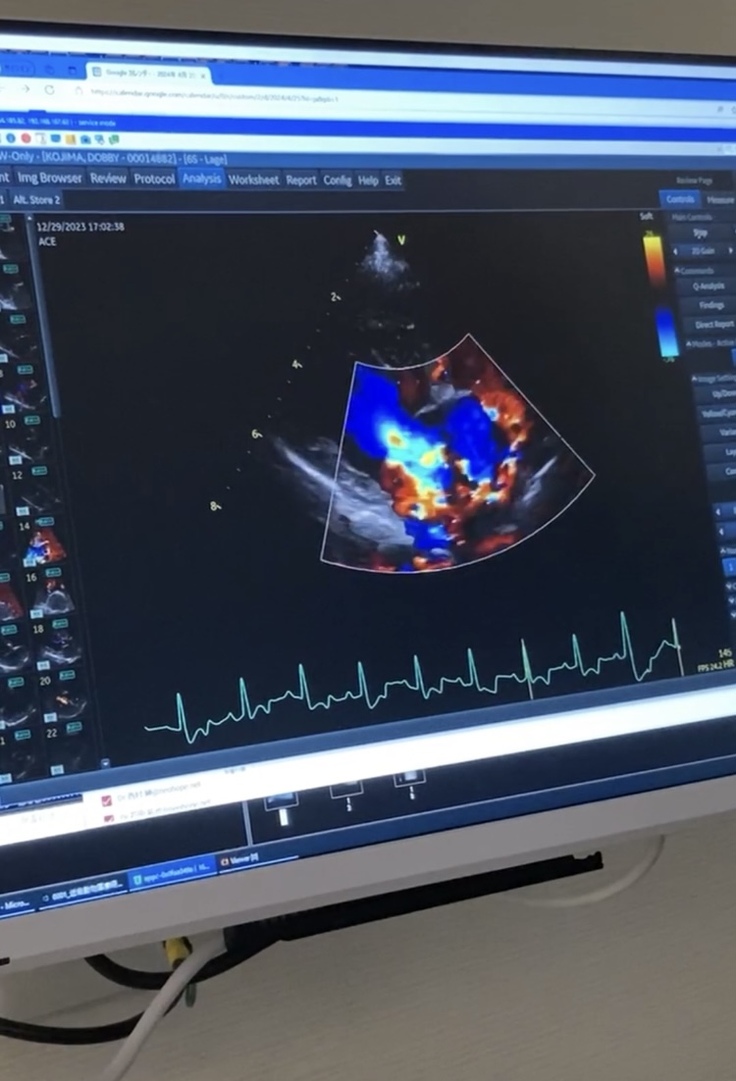

手術前の心臓 逆流する様子